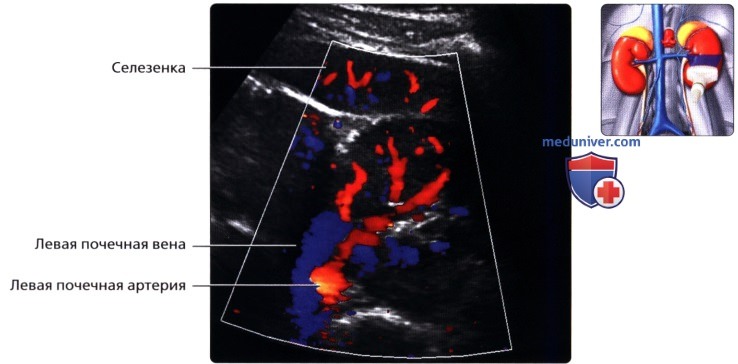

Неотъемлемой частью обследования почек стало ультразвуковое допплерографическое исследование, дающее возможность наблюдать за кровотоком в почечных сосудах. Делая УЗИ сосудов почек, можно установить на ранней стадии стеноз артерий, сбои в кровоснабжении, сосудистые сбои.

УЗДГ (УЗИ сосудов почек) выполняется в положении больного лежа на боку или сидя. Каких-то особенностей у этой процедуры нет. Врач также перемещает датчик по поверхности кожи пациента, внимательно изучая постоянно меняющиеся на мониторе изображения.

• Левая почка:

о Ее труднее визуализировать из-за газа в тонкой кишке и в селезеночном изгибе ободочной кишки

о Обычно левую почку проще визуализировать, используя заднебоковой эхографический доступ и попросив пациента немного повернуться вправо приподняв левый бок

о В сложных случаях полностью переверните пациента в положение лежа на правом боку, подложите подушку под его правый бок и попросите его поднять левую руку над головой:

— Для исследования верхнего полюса левой почки можно использовать селезенку как акустическое окно

• Почечные вены:

о Лучше всего визуализируются при поперечном трансабдоминальном сканировании

о Также могут быть видны при сканировании в фронтальной плоскости с заднебоковой поверхности